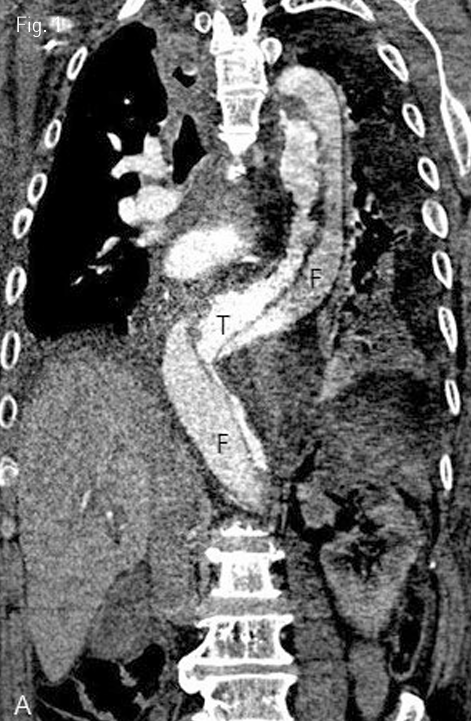

전산화 단층촬영에서 하행 흉부 대동맥 및 복부대동맥까지 박리된 Stanford type B의 대동맥박리가 확인되었으며 내막파열(intimal tear)의 위치는 좌측 쇄골하정맥의 직하방까지 였고, 박리의 범위는 하장간막동맥의 기시부까지였다. 기저에 신장동맥하부의 복부대동맥에서 양측 총장골동맥과 양측 내장골동맥까지 침범한 복부대동맥류가 있다. 양측 신장동맥은 진성 내강에서 기원하고 있었으나 좁아져 있었고, 우측 신장이 조영증강되지 않아 대동맥박리의 합병증으로 우측 신장 관류장애가 동반된 것으로 판단되었다(Fig. 1). 이를 치료하기 위하여 혈관내 대동맥 창냄술이 의뢰되었다.

Fig 1A

Contrast-enhanced CT coronal scan image (A) showed aortic dissection from aortic arch to infrarenal aorta and relationship of true lumen (T) and false lumen (F). Axial CT scan